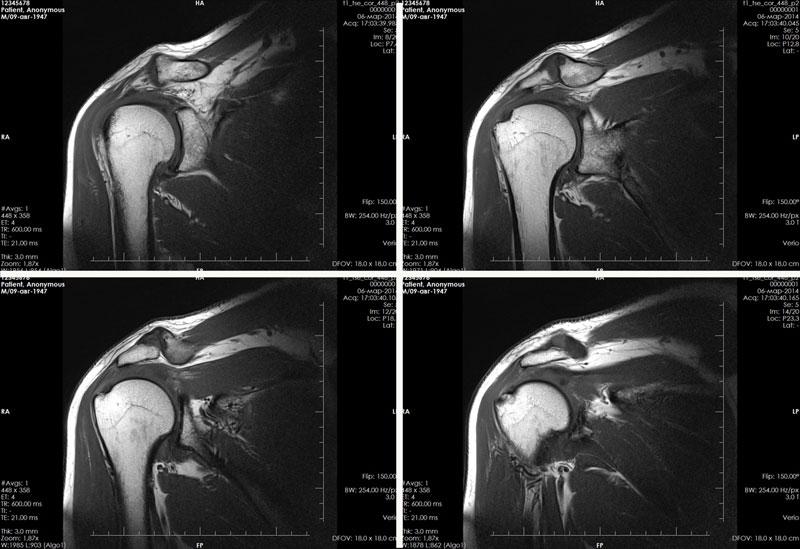

Полученные снимки в нескольких срезах исследуются сразу либо соединяются диагностом в единое трехмерное изображение исследуемой области (фото МРТ плеча представлено в материале).

Что показывает МРТ плеча? Полученные данные позволяют специалисту оценить и обнаружить следующие нарушения:

- состояние костных и мягких структур;

- трещины в хрящевой ткани;

- разрывы, растяжение сухожилий, мышц;

- наличие опухолевого процесса;

- состояние вращательной манжеты;

- различные деформации;

- выявление возможных дистрофических процессов;

- обнаружение наростов;

- выявление воспалительных и инфекционных процессов;

- наличие скопления жидкости;

- аномалии развития.

Визуализация структуры плечевого сустава на МРТ-снимках

Также может быть оценено состояние плечевого сплетения (нервные волокна, формирующие нервы плечевого пояса и свободной верхней конечности). В этом случае могут быть выявлены разрывы, сдавливание, раздражение воспаление нервных волокон, метастатические поражения, нейрофибромы.